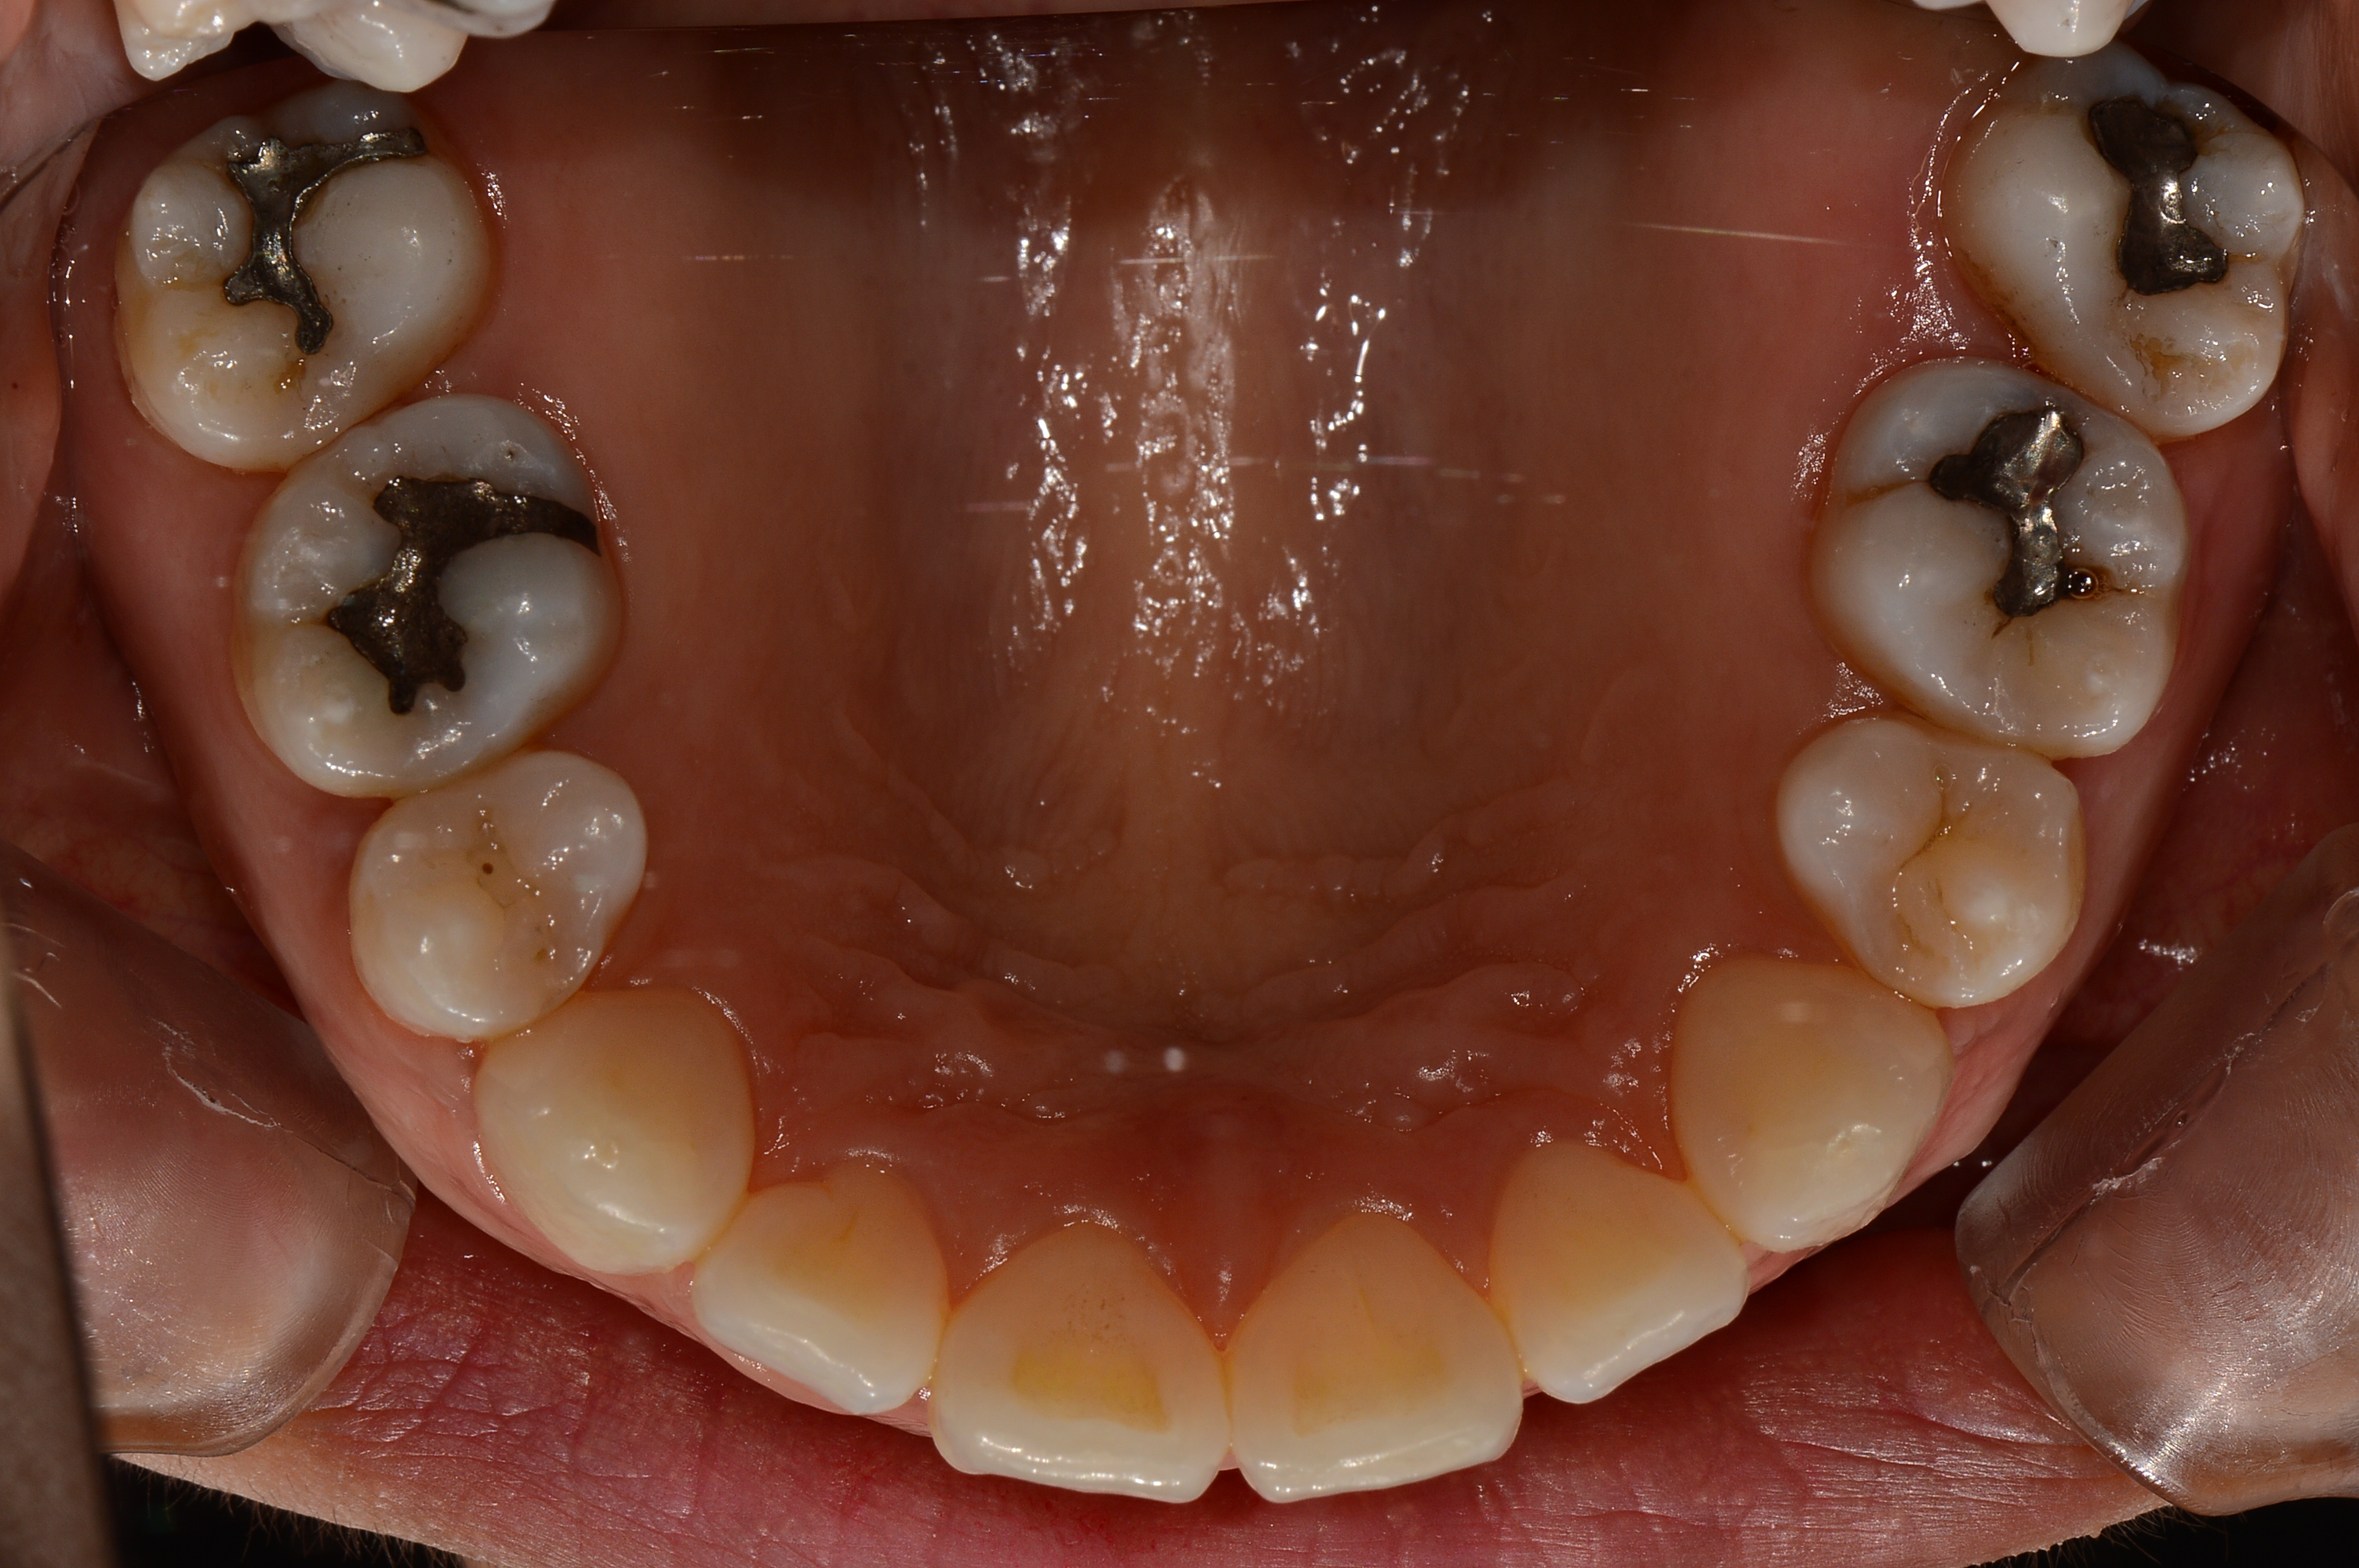

치료 전 사진입니다.